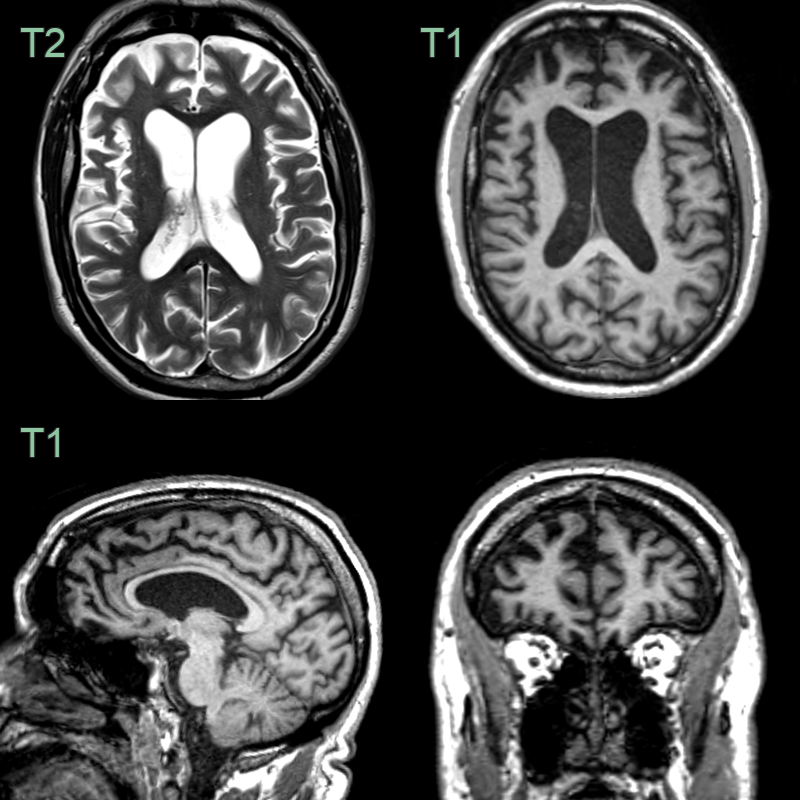

- A 60-year-old patient presented with apathy and increased weight. The patient's partner reported episodes of reckless spending in the preceeding year. The patient had a strong family history for dementia.

- MRI showed symmetrical frontal lobe atrophy. The frontal horns were larger than the trigones. The olfactory sulci were wided ("Crab sign").

- Genetic testing revealed a C9ORF72 mutation as the cause of the frontotemporal dementia.